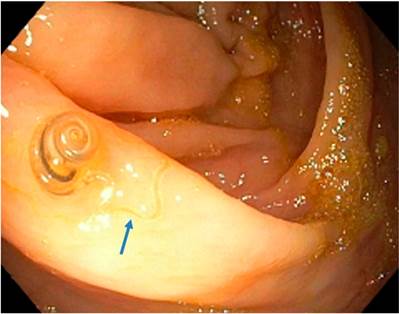

Con estas diferencias morfológicas descritas, concluimos que el T. trichiura macho tiene una curvatura pronunciada que le da una apariencia “enrollada”, pero lo más característico de este parásito es su forma de látigo o pelo en su parte anterior 7 (Figura 2), que no se evidencia en nuestro caso.

Figura 2 La flecha azul muestra la característica del parásito en forma de hilo o látigo en la parte anterior. Tomada de la referencia 7

Given the morphological differences just described, we concluded that even though a male T. trichiura has a pronounced curvature that gives it a “coiled” appearance, its most characteristic feature is its front end whip (Figure 2) which was not evident in our case. 7

Figure 2 The blue arrow shows the characteristic anterior whip of the parasite. Taken from reference 7